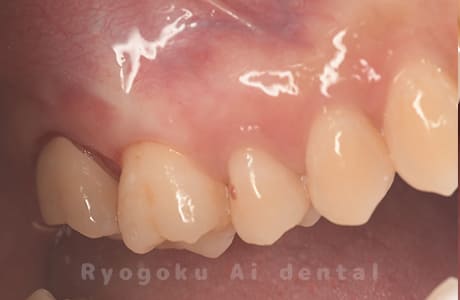

他院ではお薬の交換と抗生剤の処方で経過を診ていた患者さんです。歯茎の腫れが治らないとのことで、根管治療を開始し、2回目のご来院で腫れが引いたケースです。現在は被せ物も入り、良好に経過しております。